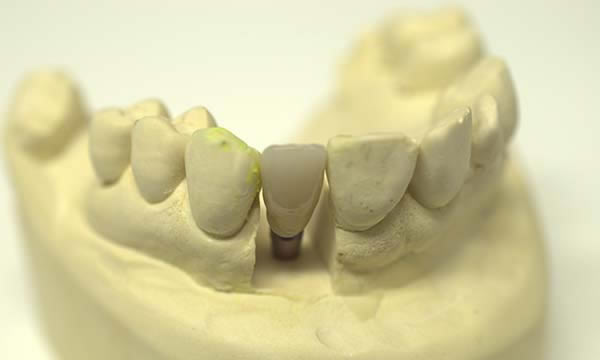

A failed apicectomy in the UL1 was diagnosed after a history of labial draining discharge and mobility. The patient was referred to us for treatment and a diagnostic wax up was used to discuss the proposed finished crown, estimated gingival margin position and crown height with the patient.

A tooth bourn position guide allowed for predictable implant placement within the aesthetic zone. Collaboration with with Smile Dental Laboratory and clinical pictures helped to produce a great shade match and natural looking result.